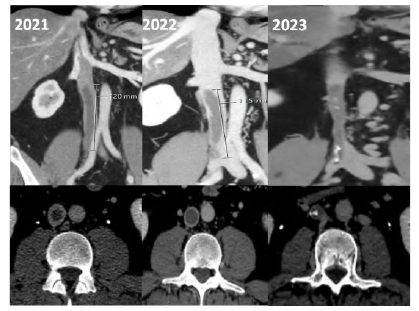

After one year, the complaints of right leg swelling and discomfort persisted, raising the suspicion of post-thrombotic syndrome. A CTA revealed a 12 cm thrombus in the infrarenal IVC, Figure 1. Despite ongoing anticoagulation, symptoms persisted with intermittent improvements and worsening. The diagnostic workup and the proposal for surgery were delayed due to circumstances caused by the COVID-19 pandemic.

Figure 1 Computed tomography angiography - coronal (top) and axial (bottom) views.Evolution over time is noted from left (2021) to right (2023).